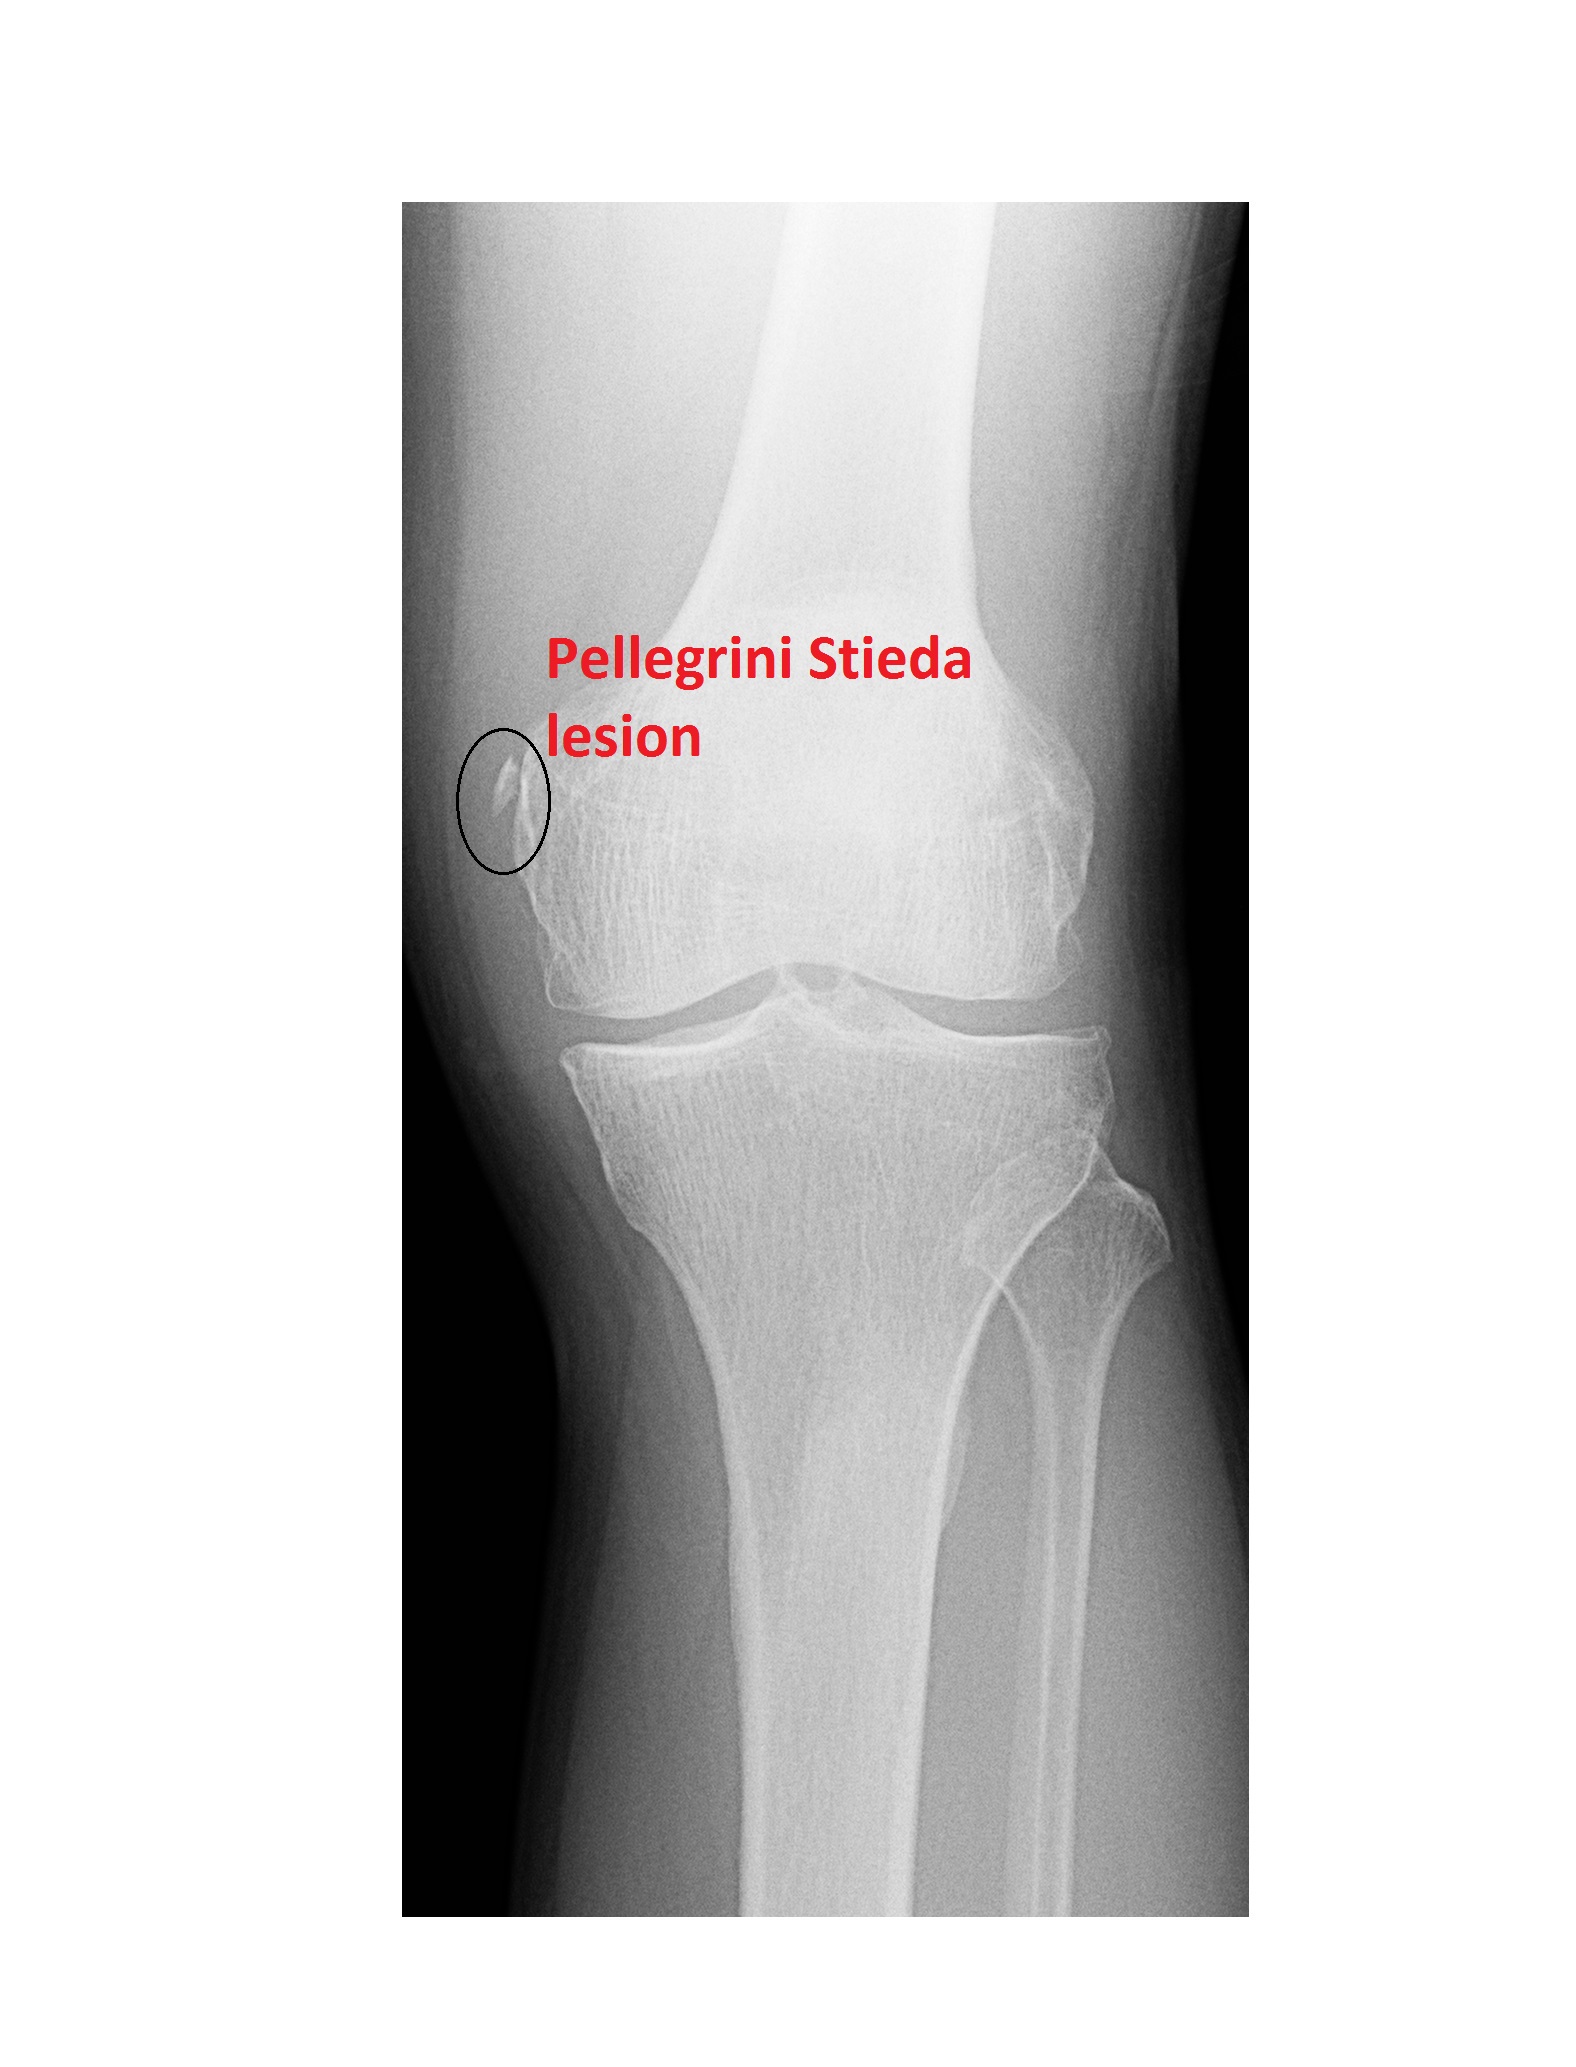

Accelerate your recovery for MCL tear with our expert guide. Discover effective physical therapy exercises, proven rehabilitation protocols, and safe return-to-sport strategies. Learn how to manage knee pain, reduce inflammation, and strengthen stabilizing ligaments to regain full range of motion. Follow these essential recovery tips to heal your medial collateral ligament injury faster and prevent future knee complications.